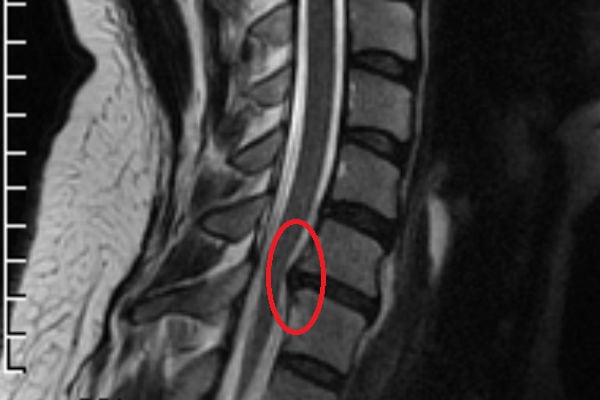

Секвестированная грыжа позвоночника справа — ядро полностью вышло за пределы фиброзного кольца

Секвестированная грыжа на снимке КТ

- Компьютерная томография или МРТ. Это самые действенные способы, которые покажут состояние позвоночника на снимках в разных проекциях. Здесь же четко видно выпячивание и деформация тканей за счет секвестрации.

Наиболее информативны в диагностировании секвестрированных грыж МРТ и КТ. На полученных изображениях хорошо просматривается выпячивание, его локализация и размеры.

Рентгенограмма показывает изменения в костных структурах позвонков, что дает возможность предположить выбухание или выпадение ядра. Наиболее точным методом при постановке диагноза является проведение исследования на МРТ, при этом обнаруживается место компрессии нервных волокон.

МРТ – это «золотой стандарт» диагностики грыж с секвестрированием, который выявляет участки поражения, локальное воспаление, точное местонахождение секвестра, расположение корешков и спинного мозга. Противопоказанием для проведения данного исследования является наличие в теле металлических (чаще стальных) имплантов и эндопротезов. В этом случае применяют такое исследование, как КТ.